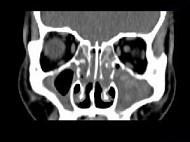

问题 男,14岁,持续性鼻塞、嗅觉减退,流脓涕数年,CT检查如图,最可能的诊断为 ( )

选项 A、恶性肉芽肿 B、上颌窦癌 C、鼻及鼻窦息肉 D、过敏性鼻炎及鼻窦炎 E、鼻炎及鼻窦炎

答案 E